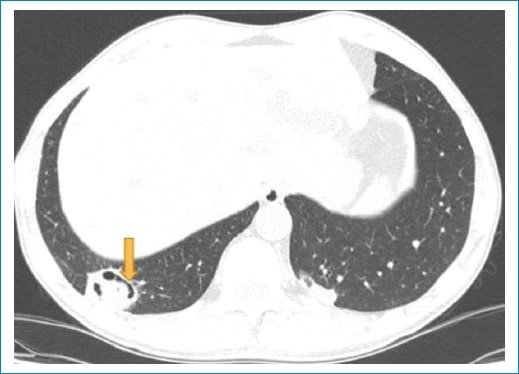

Figura 1. Tomografía computada con ventana pulmonar plano axial, opacidad nodular subpleural en el segmento basal posterior del LID que presenta cavitaciones tubulares y periféricas (flecha).

El signo del menisco pulmonar también se ha descrito como el signo del aire creciente o el signo de media luna. Corresponde a una colección de aire en forma de luna creciente que se visualiza en la radiografía y en la tomografía de tórax como una radiolucencia dentro de un área de consolidación o un nódulo; puede variar de forma, de media luna hasta encapsular totalmente la lesión (Fig. 1). Este signo radiológico, que no es patognomónico de aspergilosis, fue descripto en el año 1975 inicialmente por Bard y Hassani, quienes explicaron en un hematoma pulmonar el signo de la media luna, y en 1979 Curtis describió este signo como una forma invasiva de aspergilosis1.

Aspergillus es un hongo filamentoso conformado por cadenas celulares llamadas hifas. Fisiopatológicamente, estas alteran las paredes de los vasos sanguíneos a través de las arterias bronquiales generando oclusión de la luz vascular, lo que lleva a la necrosis y cavitación. Esto se refleja radiológicamente como un área de vidrio esmerilado, consolidación y/o nódulos peribronquiales. En su evolución el centro infartado se retrae y se reabsorbe, resultado de la reacción neutrofílica, dejando un área de tejido desvitalizado que se desprende del resto de la consolidación2. El aire que se encuentra entre el tejido desvitalizado y el parénquima consolidado que lo rodea tiene forma de media luna o del aire creciente (Fig. 2). Este signo es tardío, coincide con una recuperación progresiva de la infección y depende de la función leucocitaria, por lo cual generalmente se observa en pacientes inmunocomprometidos, que en general inician clínicamente con cuadro de hemoptisis3.